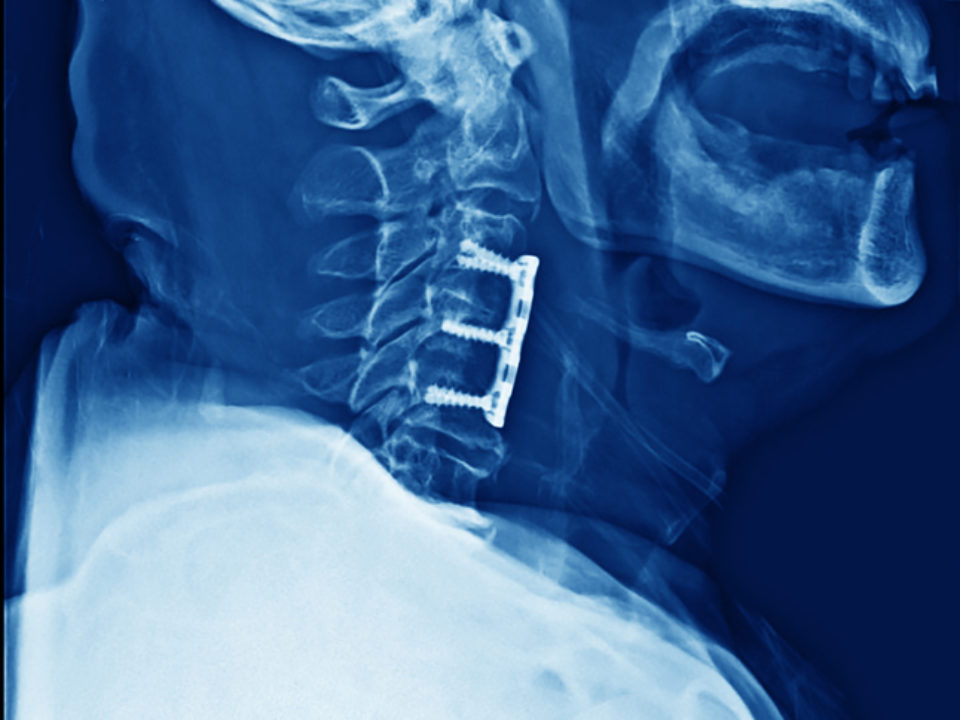

Spinal fusion (such as TLIF) is a surgical technique to stabilize the spinal vertebra and the disc or shock absorber between the vertebra. Lumbar fusion surgery is designed to create solid bone between the adjoining vertebra, eliminating any movement between the bones.

As with all spinal fusion surgery, posterior lumbar interbody fusion surgery involves adding a bone graft to an area of the spine to set up a biological response that causes the bone to grow between the two vertebral elements and thereby stop the motion at that segment.

Pain in the neck and extremities may occur when an intervertebral disc herniates – when the annulus fibrosus (tough, outer ring) of the disc tears and the nucleus pulposus (soft, jelly-like center) squeezes out and places pressure on neural structures, such as nerve roots or the spinal cord.